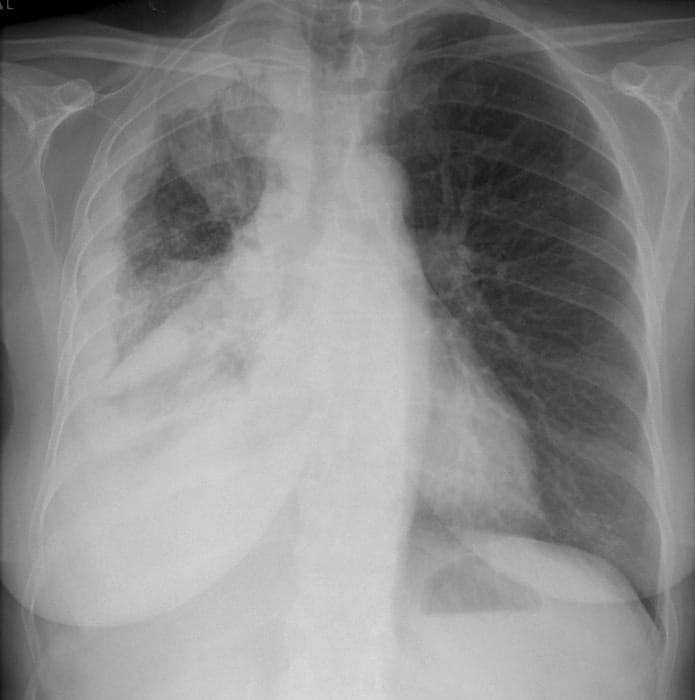

CXR Interpretation:

There is encasement of the right lung from pleural thickening in the right hemithorax with volume loss.

The left pleura is normal. There is a nipple shadow on the left.